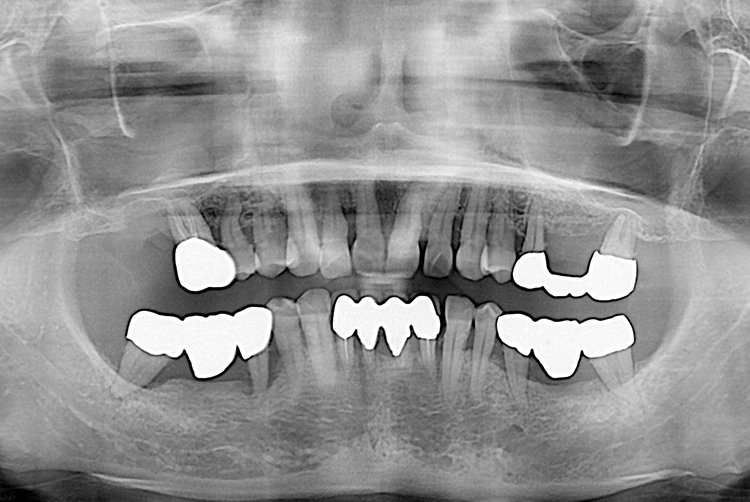

[임플란트] 임플란트

치료전 : 2015-01-27

세종치과는 많은 환자와 다양한 케이스를 바탕으로 항상 편안한 임플란트 수술을 제공하고자 노력하고,

오래동안 튼튼히 쓸 수 있는 임플란트 수술을 가장 큰 목표로 삼고 있습니다